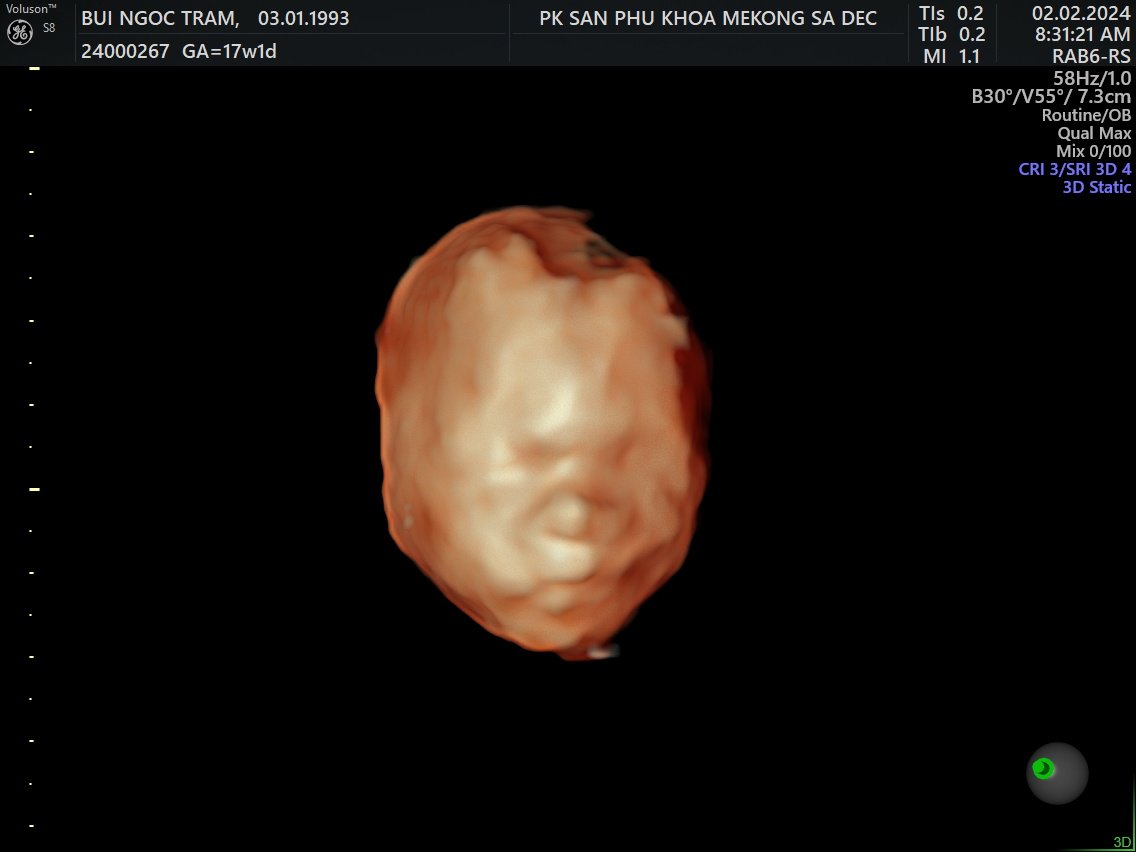

Siêu âm 5D

Tuần 17

2 Feb 2024

Về Sadec, được đi siêu âm 5DLà con trai, hơi ú và hành mẹ bị viêm bạch huyết, hên là phát hiện sớm và được bác sĩ cho thuốc!